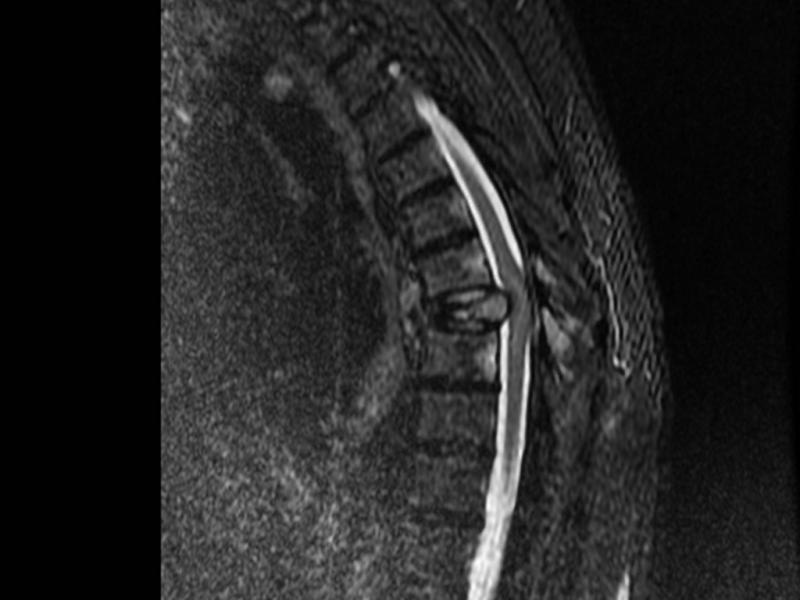

A 63 you male presents with back pain and lower extremity